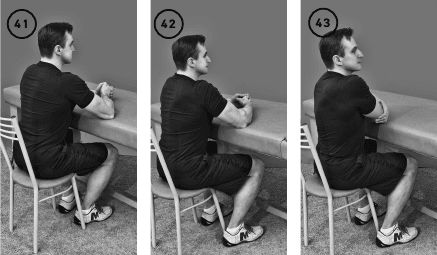

Упражнение «Шарнир – локоть наружу»

Исходное положение – сидя за столом, обе руки согнуты в локтевых суставах под прямым углом, помещаются предплечьями на стол и упираются локтями в стол, подобно шарниру. Правая кисть сжата в кулак, левая обхватывает ее снаружи.

Фаза изометрического напряжения: вы пытаетесь отвести правый кулак наружу, опираясь на локоть, как на шарнир. Левая рука препятствует этому движению. Удерживаете состояние изометрического напряжения мышц, вращающих плечо наружу, в течение 20–30 секунд.

Фаза растяжения: левой кистью обхватываете правое плечо чуть выше локтя и тянете руку вниз и влево, растягивая мышцы плеча, области лопатки в течение 10–20 секунд. Повторить 1–3 раза. Выполнить для противоположного плеча (ил. 41–43).